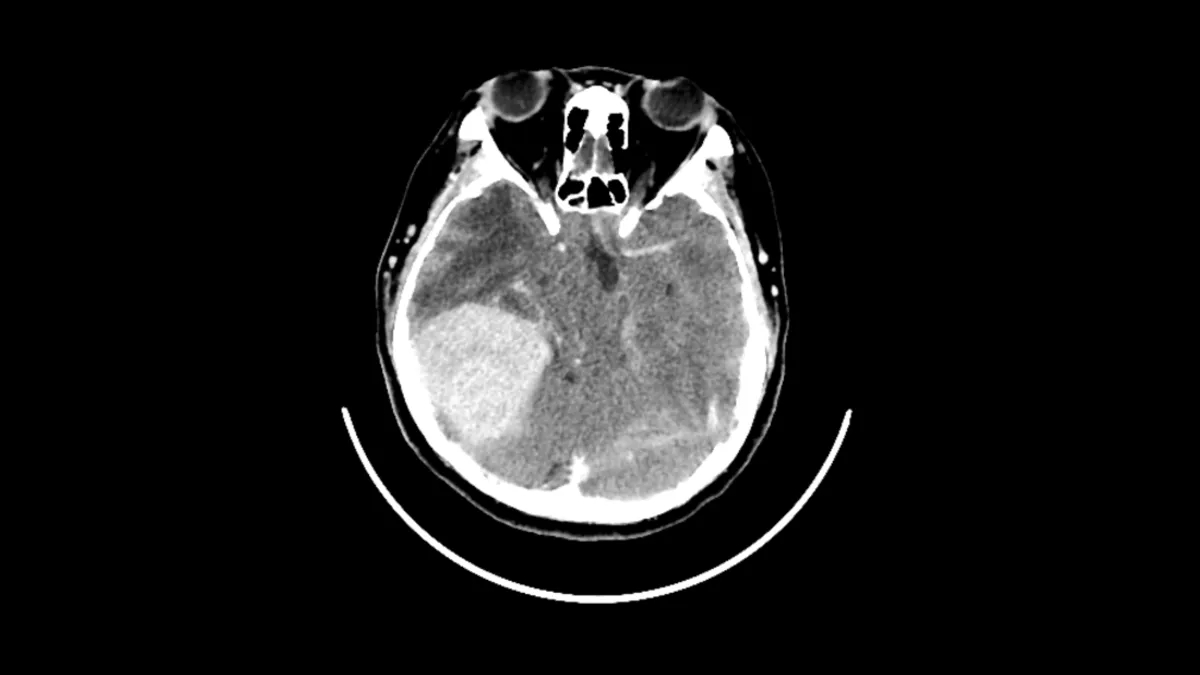

Yapılan beyin taraması tıp ekibini şaşkına çevirdi. Görüntülerde kadının beyninde menenjiyom adı verilen oldukça büyük bir tümör bulunduğu ortaya çıktı. Daha da dikkat çekici olan ise kadının bu büyüklükteki bir kitleye rağmen şiddetli baş ağrısı, görme kaybı veya nörolojik bozukluk gibi tipik belirtiler göstermemiş olmasıydı.